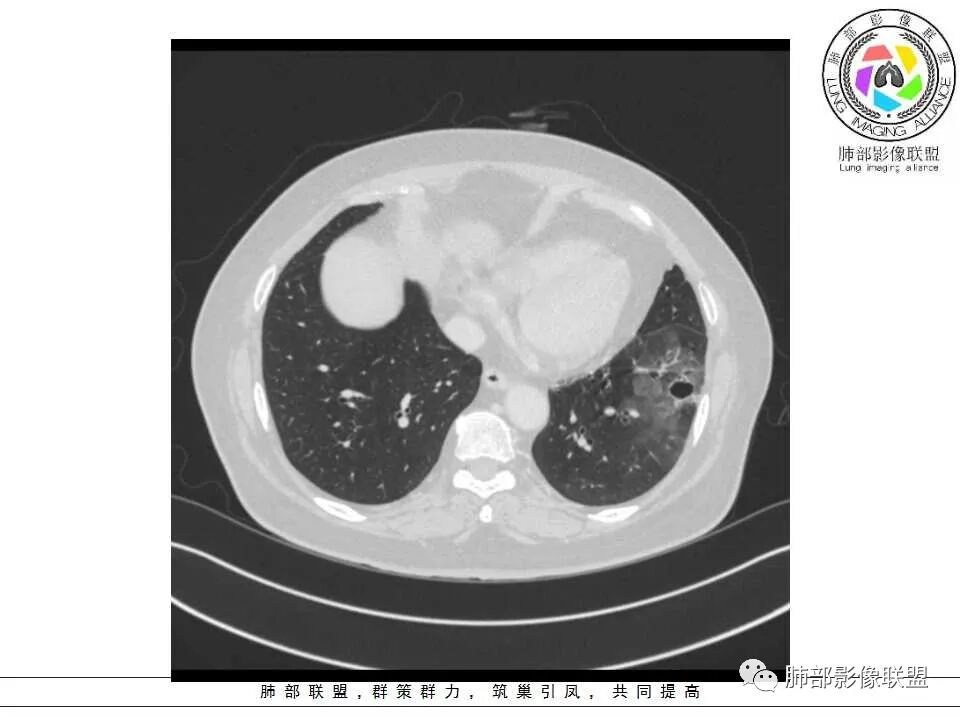

女性,65岁,咳嗽、咳痰2月余,伴发热数日。

胸CT:左肺下叶囊腔,壁厚薄不均,可见壁结节,囊腔内可见断裂小梁,部分融合,周围边界较清楚GGO,胸膜牵拉,可见血管集束、支气管充气征,冠状位部分层面可见支气管在囊腔边缘截断。考虑:囊腔型腺Ca。鉴别:肺大疱感染,CPAM等。

患者,女,65岁,2月余前受凉感冒后开始出现咳嗽,咳白痰,初发热2天,体温38℃左右,后降至正常,咳嗽无好转。近2日咳嗽加重,痰量增多,为黄白痰,无发热,无乏力、盗汗,无胸痛、胸闷,无头晕、头痛,无恶心、呕吐。PET-CT检查提示炎性病灶与恶性结节鉴别困难。

1、左肺下叶外基底段不规则囊腔样病灶,囊腔内有条形影及血管穿行。

2、囊壁薄厚不均匀,稍显僵硬,有壁结节(对应边缘分叶等)、结节强化明显。

以上两条几乎将肺囊肿彻底排除在外,且高度怀疑新生物!

3、灶周环以大范围磨玻璃影,非常均匀,没有重力分布趋势,分叶状,边界隐约可变。

4、冠状位部分层面可见支气管在囊腔边缘截断。

囊腔型肺癌主要为腺癌,少数为鳞癌。

本例囊腔性病灶尽管腔壁稍显僵硬,壁结节凸显,但女性患者,灶周明显磨玻璃晕,都强烈提示为囊腔性腺癌。